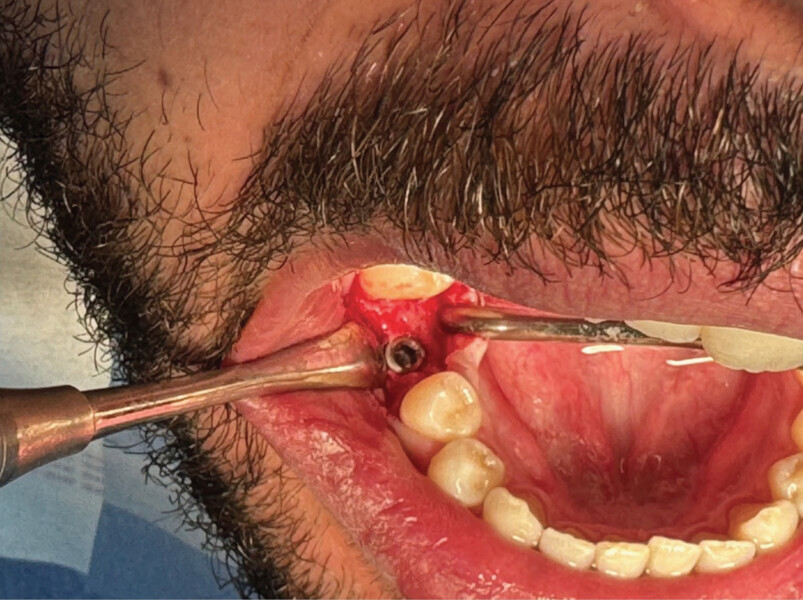

L’avulsion a été faite après anesthésie avec une ampoule de SEPANEST 40 mg adrénaline à 1/200000e. L’acte chirurgical est réalisé de manière la plus atraumatique possible, exérèse et curetage du kyste apical, nettoyage de l’alvéole. Dans ce cas précis, nous n’avons rien mis dans l’alvéole car les quatre murs alvéolaires ont pu être conservés. Un léger décollement des muqueuses vestibulaires et linguales a été nécessaire pour la mise en place de la membrane R.T.R.+.* La structure de cette membrane est faite pour être positionnée dans un sens précis, la surface lisse est toujours positionnée vers l’extérieur et la face rugueuse en regard de l’os.

C’est sa structure et composition spécifique qui va permettre la non-compétition cellulaire et par la même la constitution de l’os sous la membrane. Les cellules épithéliales vont, quant à elles, se développer en tapissant la surface lisse de cette membrane (Figs. 2 et 3).

On pourra remarquer que la membrane a été volontairement laissée exposée, afin de ne pas lever de lambeau vestibulaire ou lingual. Grâce à ceci, nous avons pu conserver la totalité de cette muqueuse attachée, ce qui nous permettra d’obtenir un résultat esthétique bien meilleur lors de la reconstruction prothétique, qu’elle soit traditionnelle (bridge ou prothèse amovible) ou sur implants, en permettant d’avoir un profil d’émergence le plus proche possible du naturel (Figs. 4–8).